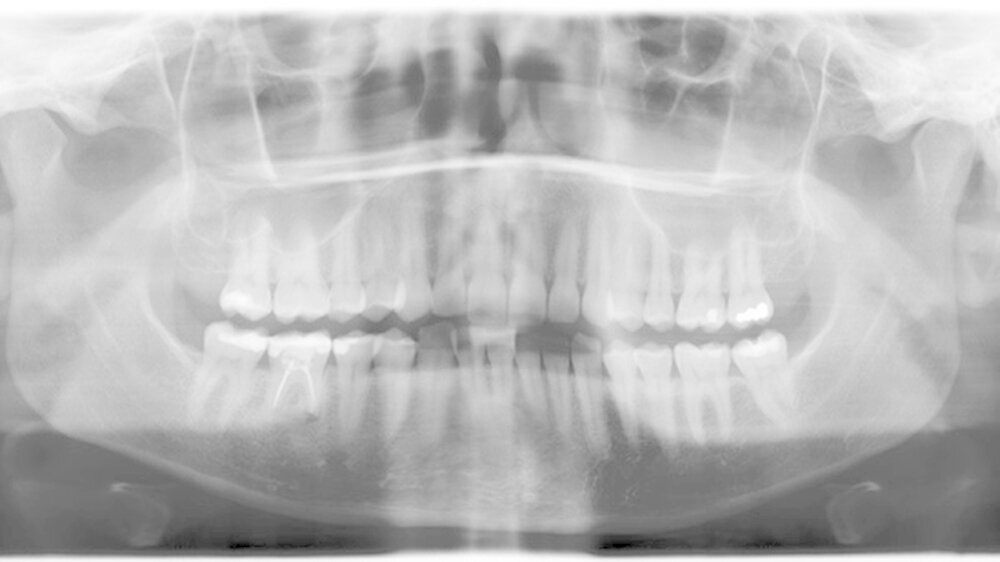

Anamnestisch wurde einen Monat zuvor eine Füllungstherapie beim Hauszahnarzt am Zahn 37 durchgeführt (Abbildung 1). Die Beschwerden seien zum ersten Mal etwa drei Tage nach der Zahnbehandlung aufgetreten und hätten sich kontinuierlich verschlimmert.

Der M. pterygoideus medialis sinister war mäßig druckdolent. Das Gebiss war sowohl konservativ als auch prothetisch vollständig saniert und gepflegt. Alle Zähne im zweiten und dritten Quadranten, inclusive des Zahnes 37, waren vital und perkussionsnegativ.